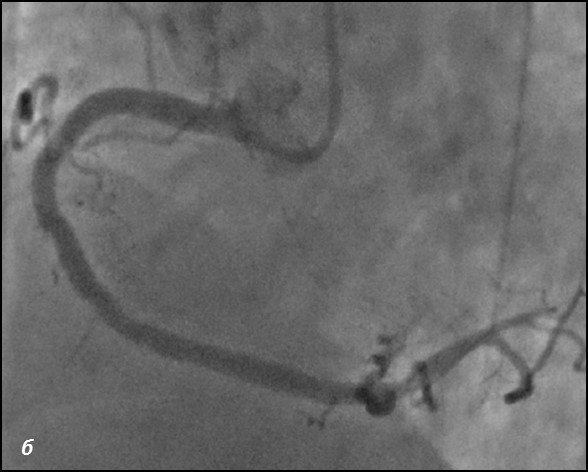

До проведения реваскуляризации миокарда пациент получал двойную антиагрегантную терапию (клопидогрел 75 мг, ацетилсалициловая кислота - 300 мг ежедневно). Чрескожное коронарное вмешательство было разделено на два этапа. Первым этапом – планировалось выполнить реканализацию и стентирование ПМЖВ, вторым – стентирование ПКА. Однако по данным повторной коронарографии было выявлено сужение тела ствола левой коронарной артерии (ЛКА) на 30%, окклюзия от устья передней межжелудочковой артерии (ПМЖВ), постокклюзионный сегмент заполнялся по слабым внутри- и межсистемным коллатералям, устьевое сужение огибающей артерии (ОВ) 60%, окклюзия средней трети правой коронарной артерии (ПКА), постокклюзионный сегмент заполнялся по внутрисистемным перетокам. Показатель Syntax Score для данного пациента составил 34.5. Учитывая, что по данным ранее выполненной коронарографии, правая коронарная артерия оставалась проходимой, а передняя межжелудочковая ветвь была окклюзирована и на момент реваскуляризации срок окклюзии составлял 7 лет, была проведена сменена тактики и первым этапом выполнена реканализация правой коронарной артерии, а спустя 2 суток – реканализация и стентирование передней межжелудочковой ветви от устья с баллонной ангиопластикой огибающей ветви (рис.1,2). Учитывая, что проводилась реканализация хронической окклюзии, в обе коронарные артерии были имплантированы стенты с лекарственным покрытием Resolute ONYX (Medtronic).

Рис.1 Ангиограмма правой корнарной артерии. а) при коронарографии правой коронарной артерии –артерия окклюзирована от уровня п/3 (стрелка); б) проходимость по правой коронарной артерии полностью восстановлена; в) после выполненной реканализации и стентирования ПКА отмечаются межсистемные перетоки в ПМЖВ-ЛКА (стрелка)